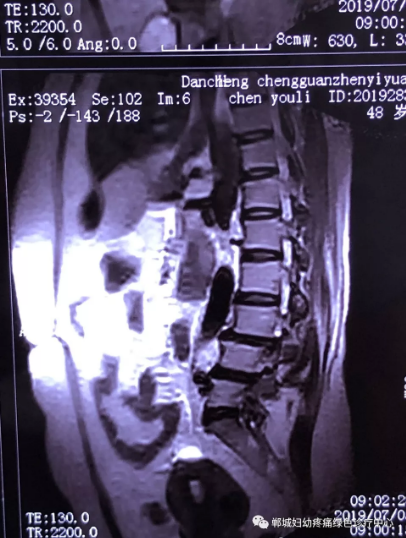

2年前,雙樓鄉(xiāng)的陳女士不小心摔了一跤后出現(xiàn)腰痛,當(dāng)時(shí)到藥店買(mǎi)了膏藥來(lái)貼,疼痛減輕了一些,但是從此以后反反復(fù)復(fù)出現(xiàn)腰痛。到處進(jìn)行治療,不見(jiàn)好轉(zhuǎn),最近腰痛加重了,痛得受不了,出現(xiàn)行走后甚至持續(xù)的雙下肢后側(cè)或后外側(cè)放射性的疼痛麻木、間歇性跛行等癥狀。陳女士趕忙去醫(yī)院治療,做了磁共振檢查后確診為腰椎滑脫、腰椎反弓。醫(yī)生都告訴她需要手術(shù)治療。隨后她又帶著片子咨詢了好幾家醫(yī)院,結(jié)果都是一樣,她已經(jīng)做好了手術(shù)的打算。

治療前